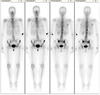

Tc99m MDP bone scan Osteoid osteoma Bone scan demonstrates a double density sign, with a focal region of intense uptake, superimposed on a larger area of generalised increase activity.

194

Tc99m MDP bone scan Metastatic prostate cancer Multiple areas of hyperactivity mainly in axial skeleton (metastases) in a patient with known prostate cancer.

195

Tc99m MDP bone scan Renal osteodystrophy Anterior and posterior planar images from a Tc-99m MDP whole body bone scan demonstrate diffusely increased radiotracer uptake throughout the axial and appendicular skeleton. Especially intense activity is noted in the mandible and maxilla. There is absent renal and bladder activity.

196

Tc99m MDP bone scan Calcaneal stress fracture Intense increased uptake in the left calcaneum

197

Tc99m MDP bone scan Hypertrophic osteoarthropathy Whole body bone scan demonstrates symmetric increase uptake in the diaphyses and metaphyses of the tubular bones of the appendicular skeleton along the cortical margin, matching the findings on X-ray and CT.

198

Tc99m MDP bone scan Breast cancer skeletal metastases Delayed planar whole body planar and spot views demonstrate multiple foci of increased tracer accumulation in the axial and proximal appendicular skeleton. Lesions are most numerous in the pelvis, with the most intense lesions seen in bilateral posterior iliac bones and the left iliac crest.

199

Tc99m MDP bone scan Paget disease of the tibia Diffuse uptake in expanded left tibia, commences from proximal articular surface. No abnormal focal uptake to indicate metastatic disease. Degenerative pattern of uptake in spine, shoulders and left first MTP joint.

200

Tc99m MDP bone scan Vertebral compression fracture On the early phase blood pool image, there is minor focal hyperaemia in the right lower thoracic spine, seen best on the posterior image. On planar delayed phase imaging, there is focally increased tracer accumulation in the lateral aspects of the T11 vertebral body. There is also incidental intense periarticular uptake in the medial compartments of both knees (right greater than left).

201

Tc99m MDP bone scan Osteomyelitis On early phase imaging, there is increased blood flow to the left leg, with particular hyperaemia in the region of the distal femoral metaphysis. On delayed phase imaging, there is intense tracer accumulation in the corresponding left distal femoral metaphysis, most marked anteromedially. The left distal femoral physis also demonstrates more intense tracer accumulation compared to the left. Tracer distribution elsewhere is physiological only.